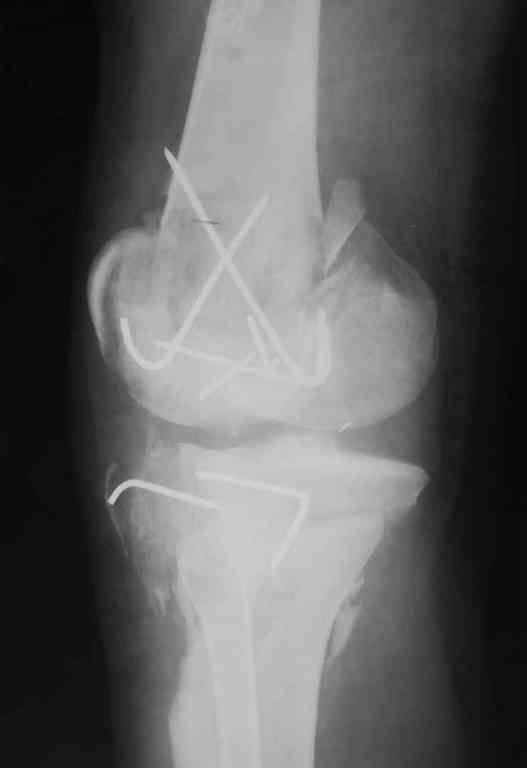

Re: Последствия открытого перелома дистального отдела бедра

Пожалуйста, снимки.